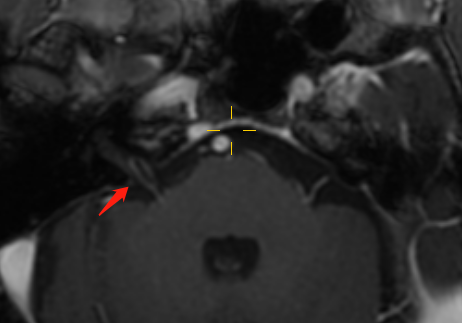

左侧小脑下前动脉于内耳道外口穿行于面神经和前庭耳蜗神经间隙,局部接触但无形态改变